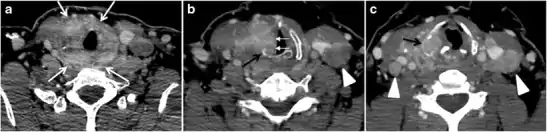

Thyroid lymphoma represents about 5% of thyroid malignancies. Non-Hodgkin's lymphoma is the most common type and can be secondary to generalized lymphoma or a primary tumour. Primary thyroid lymphoma usually pre-exists with Hashimoto's thyroiditis. On CT scans with and without contrast, lymphomas tend to have low attenuation values. Thyroid lymphomas have a variable appearance and mostly manifest as a solitary mass (80%). They may also manifest as multiple nodules (15% to 20%) or as a bulky mass replacing the entire gland with extra-thyroid extension (Figs. 11 and and12).12). The presence of cervical lymphadenopathy supports such a diagnosis. Although it is uncommon, tumour necrosis has been reported.[1]

Goiter

A goiter is an abnormal thyroid gland proliferation that manifests as multi-nodular, uni-nodular, or non-nodular diffuse glandular enlargement. A goiter is formed of solid matrix, colloid cysts, blood products, calcification, and fibrosis, and this heterogeneity may lead to variable appearances on a CT scan (Figs. 13, 1414 and and15)15). The US is more sensitive in evaluating thyroid nodules within a goiter; however, a symptomatic goiter may require surgical treatment with total thyroidectomy, and in this case CT plays an additional role in preoperative evaluation. Specific aspects for examination on a CT scan during the preoperative evaluation for goiter include extension, mass effect, and suspicious features of malignancy.[1]

Malignancy can coexist within the goiter and a CT scan may give a clue if there are abnormal cervical lymph nodes and/or signs of invasion. Retrosternal extension (Fig. 15) could affect the surgical approach, as a lower extent may require a partial or total sternotomy to facilitate complete resection. Therefore, the distance of the retrosternal extent from the sternal notch should be measured on a sagittal image.[1]

The interpreting radiologist should describe the mass effect, detailing its degree and direction of displacement of central structures, including the trachea, oesophagus, larynx, and pharynx. Attention should be directed to the upper extent of the goiter and structures immediately surrounding the thyroid gland, including the neuro-vascular structures, retropharyngeal space, and pre-vertebral space. The reporting radiologist should evaluate the vocal cords for symmetry and signs of vocal cord palsy.[1]